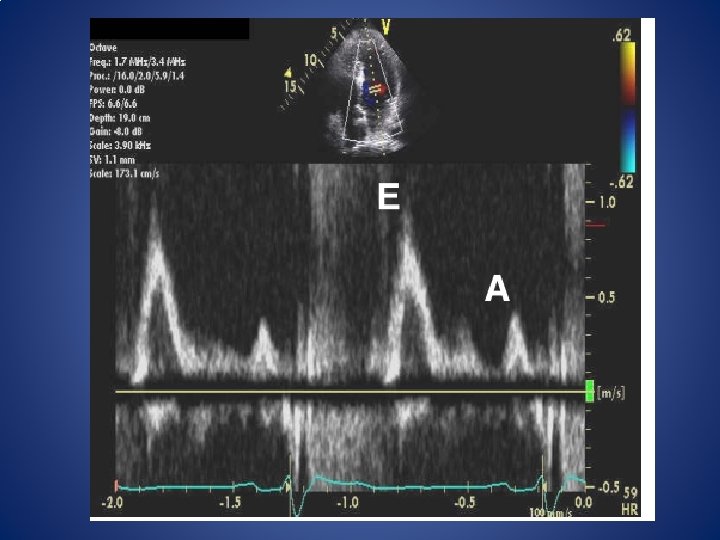

Acquisition of mitral inflow • apical 4 chamber, PW • 1 mm – 3 mm sample volume between mitral valve tips • initially obtained at sweep speeds of 25 to 50 mm/s for the evaluation of respiratory variation of flow velocities • If variation is not present, the sweep speed is increased to 100 mm/s, at end-expiration, averaged over 3 consecutive cardiac cycles

Mitral inflow Primary measurements • the peak early filling (E-wave) • late diastolic filling (A-wave) velocities • the E/A ratio • deceleration time (DT) of early filling velocity • the IVRT derived by placing the cursor of CW Doppler in the LV outflow tract to simultaneously display the end of aortic ejection and the onset of mitral inflow

Mitral inflow Secondary measurements • mitral A-wave duration (obtained at the level of the mitral annulus) diastolic filling time • the A-wave velocity-time integral and the total mitral inflow velocity-time integral (and thus the atrial filling fraction) • Mid diastolic flow is an important signal to recognize. Low velocities can occur in normal subjects but when increased (>20 cm/s)- represent markedly delayed LV relaxation and elevated filling pressures